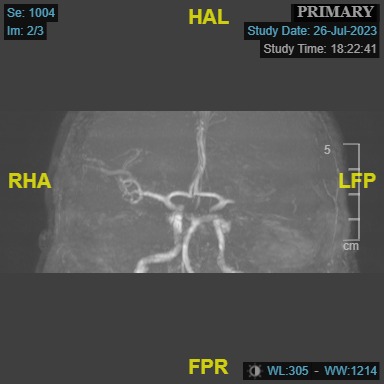

Further diagnostic workup included brain magnetic resonance imaging (MRI) and magnetic resonance (MR) angiography of intracranial vessels. The brain MRI revealed evidence of an acute infarct situated within the left middle cerebral artery (MCA) territory, affecting the left insular cortex as well as the adjacent frontal and temporal operculum (Figure 1). Additionally, the MR angiography depicted a cutoff in the M1 segment of the left MCA (Figure 2).

Promptly after admission, the patient received immediate treatment through intravenous thrombolysis with a dosage of 30 mg of tenecteplase. Subsequently, a mechanical thrombectomy procedure was conducted, employing a RED 72 reperfusion catheter (Penumbra). Following 2 passes of the catheter, a resilient clot was successfully retrieved. This intervention resulted in the complete recanalization of the MCA, leading to full perfusion of the entire left MCA territory (modified treatment in cerebral infarction score of 3, a successful recanalization). Notably, during digital subtraction angiography, an incidental finding revealed a shelf-like filling defect within the left carotid bulb, which was subsequently identified as a carotid web (Figures 3, 4, and 5).